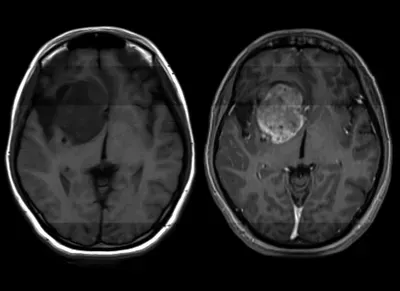

Jakarta, tvrijakartanews - Setiap tahun, lebih dari 14.000 orang di AS saja akan didiagnosis menderita glioblastoma, kanker otak yang agresif, tidak dapat diprediksi, dan tidak dapat dicegah. Masing-masing pasien baru itu akan hidup rata-rata 12 hingga 18 bulan lagi tanpa perawatan apa pun, itu bisa jauh lebih sedikit dan hanya satu dari 20 yang masih akan hidup setelah lima tahun.

“Glioblastoma adalah penyakit yang menghancurkan. Pada dasarnya tidak ada terapi yang efektif,” kata Hui Li, seorang peneliti di Departemen Patologi Fakultas Kedokteran Universitas Virginia, dalam sebuah pernyataan minggu ini. Tetapi pada tahun 2020, Hui dan rekan-rekannya mengambil langkah pertama untuk menemukannya: mereka menemukan apa yang disebut "onkogen" yang memicu perkembangan glioblastoma.